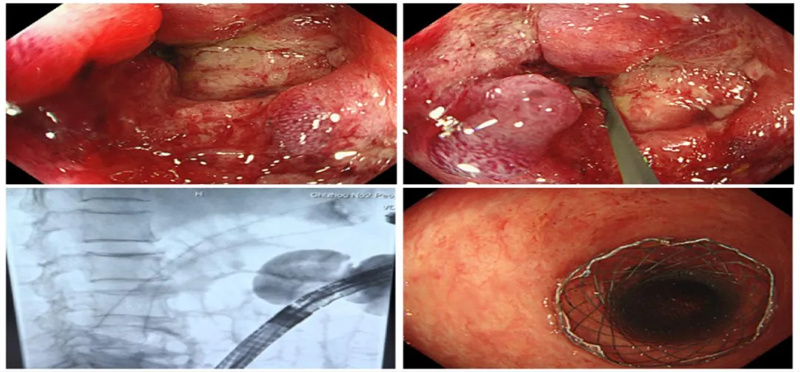

为此,医院迅速组织普外二科、消化内科、疼痛科等多学科会诊,最终确定采取DSA介入联合无痛肠镜下置入肠道支架。该方式不仅提高了手术成功率,也使支架放置更加精准可控。

术前,普外二科团队针对患者病情进行了全面评估,制定了详细的诊疗方案、术中应急预案及术后并发症的处理预案。术中,在疼痛科朱华忠主任团队的全程监护和麻醉支持下,吴斌主任利用肠镜通过狭窄肠管准确找到梗阻部位,胡永毅主任和栾谋兵医生协同操作,精准将支架送达梗阻部位并成功释放,在堵塞的肠腔中撑开一条通畅通道,为患者打通了“生命通道”。术后第三天复查显示支架扩张良好,位置稳定,患者目前已可正常饮食并顺利出院。